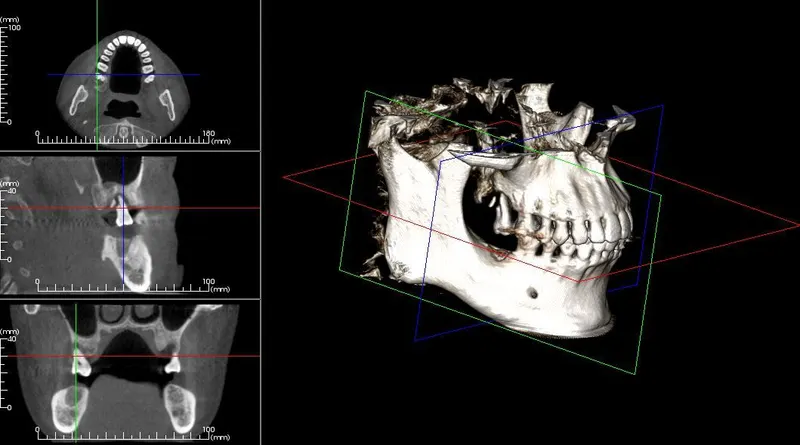

Case3